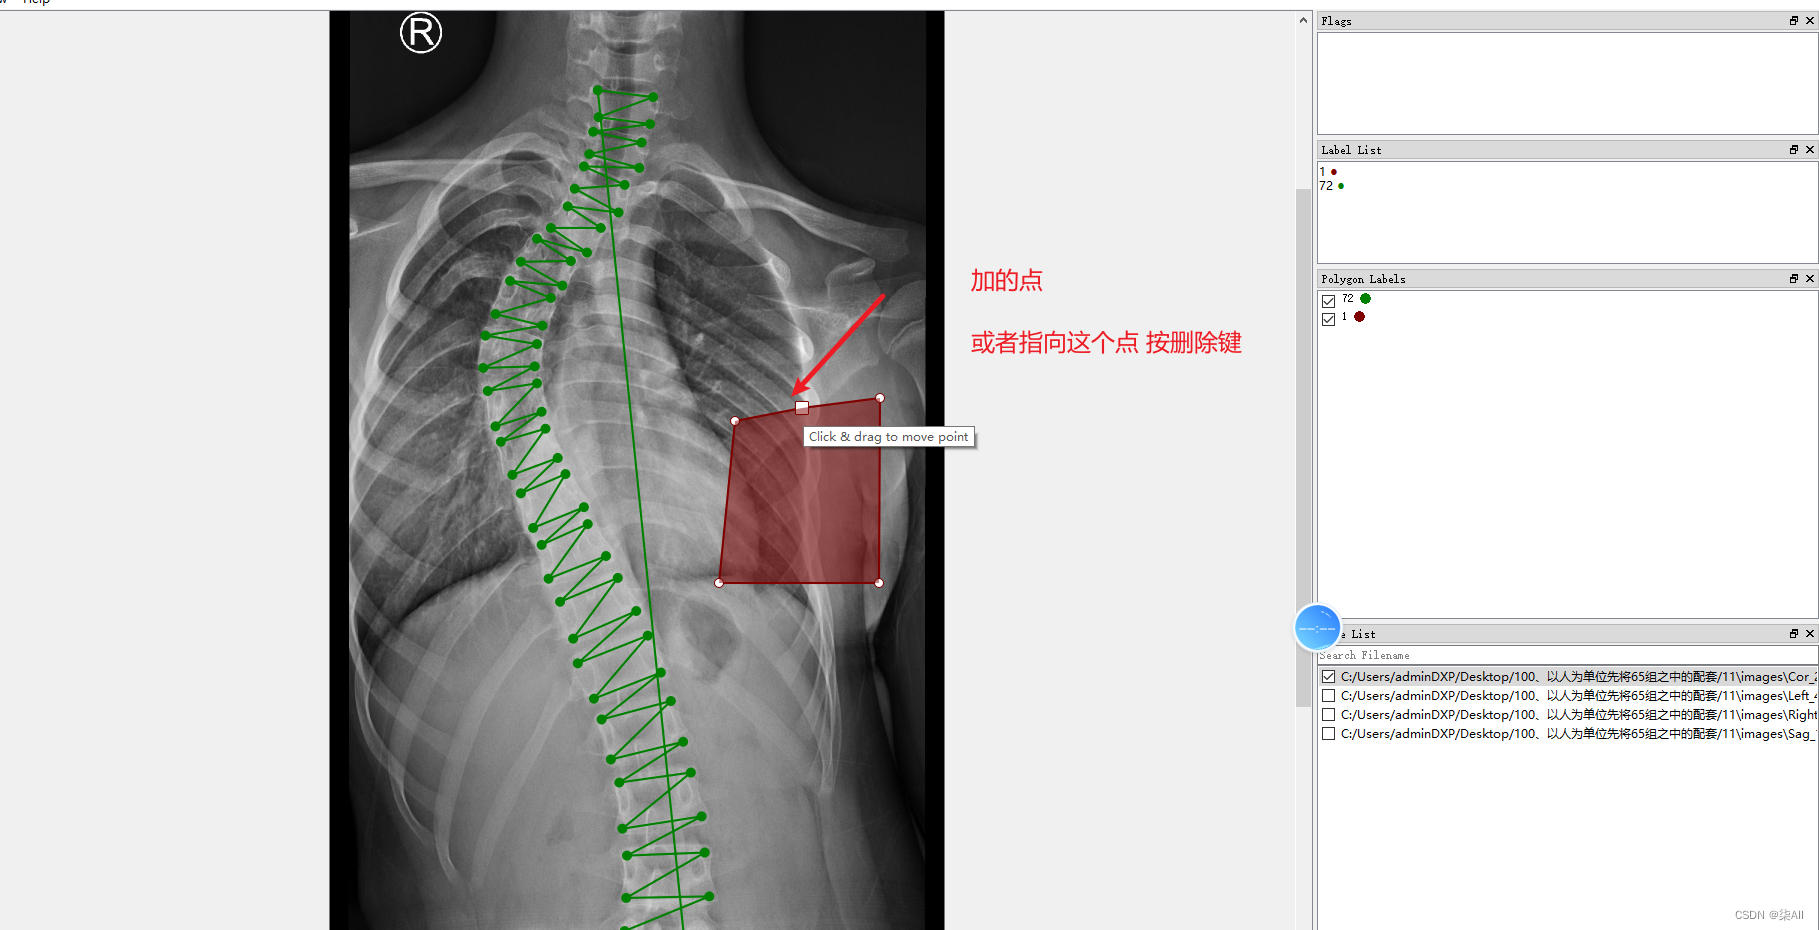

4.1、关键点不小心标注的位置不对

4.2 少标记或者多标记点。进行补点或者进行删除